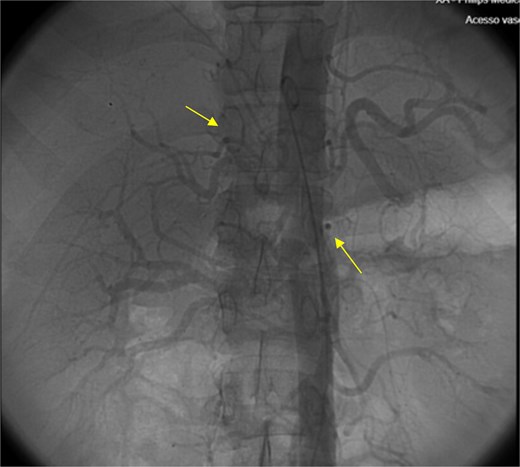

The patient presented at our Emergency Department with a sudden, diffuse, intense abdominal pain. Upon physical examination, the patient’s blood pressure was measured at 132/76 mmHg, heart rate of 103 bpm and a temperature of 39.4°C. The abdominal examination showed a rigid abdomen, with diffuse tenderness, suggesting an acute abdomen scenario. Laboratory tests revealed elevated inflammatory parameters. A abdominal and pelvic computed tomography scan revealed pneumoperitoneum and free fluid in the right iliac fossa and pelvis (Fig. 1). An exploratory laparotomy was proposed and the intraoperative findings included a sigmoid colon perforation with faecal peritonitis. They proceed with sigmoidectomy and temporary abdominal closure, planning for a reintervention to restore gastrointestinal continuity. This was done, after 48 h, through mechanical latero-lateral colo-colic anastomosis. The histopathological examination confirmed diverticulosis with perforation. The patient was subsequently transferred to the intensive care unit, for 5 days. Posteriorly, he developed severe left lumbar pain and hypertension unresponsive to medication. A CT scan revealed left kidney acute ischemia due to left renal artery thrombosis (Fig. 2). Broad-spectrum antibiotic therapy and anticoagulation, was initiated, after assessment by the Vascular Surgery and Urology teams. During his hospitalization, the patient experienced additional thrombotic events, such as occlusion of the left radial artery, and right lower lobar pulmonary embolism. A workup for prothrombotic conditions was conducted, including tests for thrombophilia, lupus, cardiolipins, antinuclear antibody, total protein test, and immunoglobulins, all of which were negative. An angiography of the abdominal aorta revealed arterial microaneurysms in the splanchnic territories: hepatic, perigastric and mesenteric arteries, suggesting polyarteritis nodosa (Fig. 3). Echocardiogram showed no abnormalities. The patient also underwent a study of the left shoulder due to repetitive pain complaints, with a suspected rupture of the rotator cuff. Electromyography excluded peripheral nerve damage. No other complications were reported. The patient was discharged on the 21st day after surgery, under anticoagulation therapy and steroids due to a suspected diagnosis of polyarteritis nodosa. Twenty-seven days after surgical intervention, the patient returned to the ED, presenting with abdominal pain in the lower quadrants and nausea. He was hemodynamically stable with abdominal pain and tenderness on the left flank and iliac fossa. Laboratory tests revealed leukocytosis and hyperlactacidemia. The CT scan reported free fluid, free gas bubbles adjacent to the sigmoid which had a concentric circular thickening of the wall, just distal to the previous anastomosis (Fig. 4). An exploratory laparotomy was performed, during which a large hematoma on the wall of the left colon was identified, with no apparent signs of perforation. A peritoneal lavage, drainage, and a derivative ileostomy were carried out. During the post-operative period the patient maintained a small volume of purulent discharge through the abdominal drain, with no abdominal tenderness. A reevaluation CT scan was performed, highlighting a regression of the hematoma of the colonic wall but raised suspicion of a low output fistula near the anastomosis. Since the patient maintained hemodynamic and analytical stability, he was discharged from the hospital with home care, including an abdominal drain, parenteral nutrition, empirical antibiotic therapy, and gradual reduction in the steroid dosage. The patient was referred to the ED, on Day 6, due to enteric drainage. An enterocutaneous fistula was diagnosed, and he was readmitted. He received 12 days of full-dose parenteral nutrition, which reduced the fistula output and improved his clinical and analytical status. Due to residual drainage volume and an analytical and imagiologic improvement, the drain was removed, and the patient was discharged, tolerating an oral diet, and with a functioning ileostomy.

(a) Pneumoperitoneum (arrowheads). (b) Free fluid in the right iliac fossa (arrowhead). (c) Free fluid in the pelvis (arrowhead).